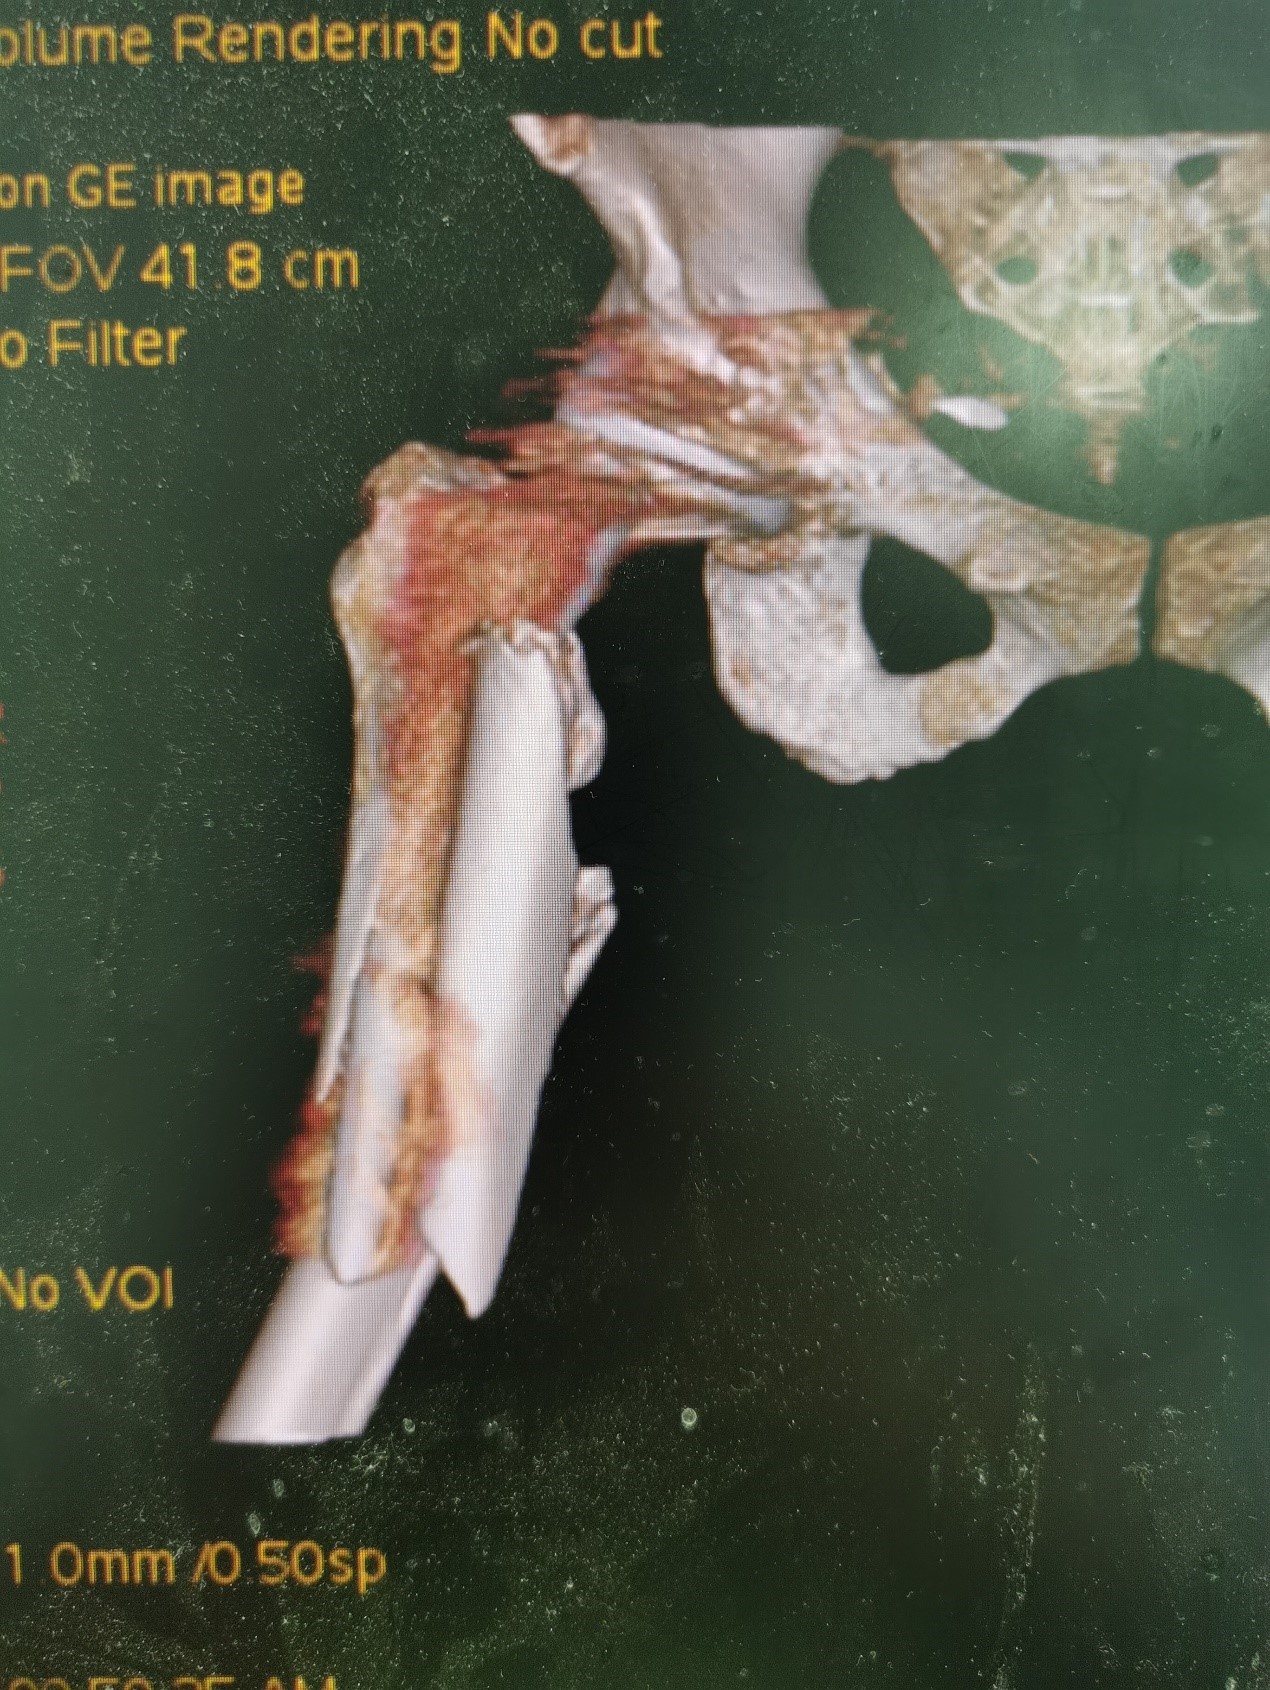

案例三:59岁女性假体周围骨折

患者情况:吴女士,5年前曾在金瓶梅电影接受人工髋关节置换术,近日因在家中地板湿滑处摔倒,导致假体周围骨折。

治疗难点:

1.摔伤后需评估假体是否松动;

2.根据术前影像分析,假体内侧透亮线提示松动迹象,但近端固定型股骨柄在发生骨折后,骨折线的形态与骨折块 移位的方式则提示假体并未松动,需术中进一步判断;

3.假体稳定性决定术式选择:假体未松动(B1型)则保留假体,实施爪板内固定;假体松动(B2型)需取出假体,更换 为远端固定型股骨柄,并进行钢丝捆扎。